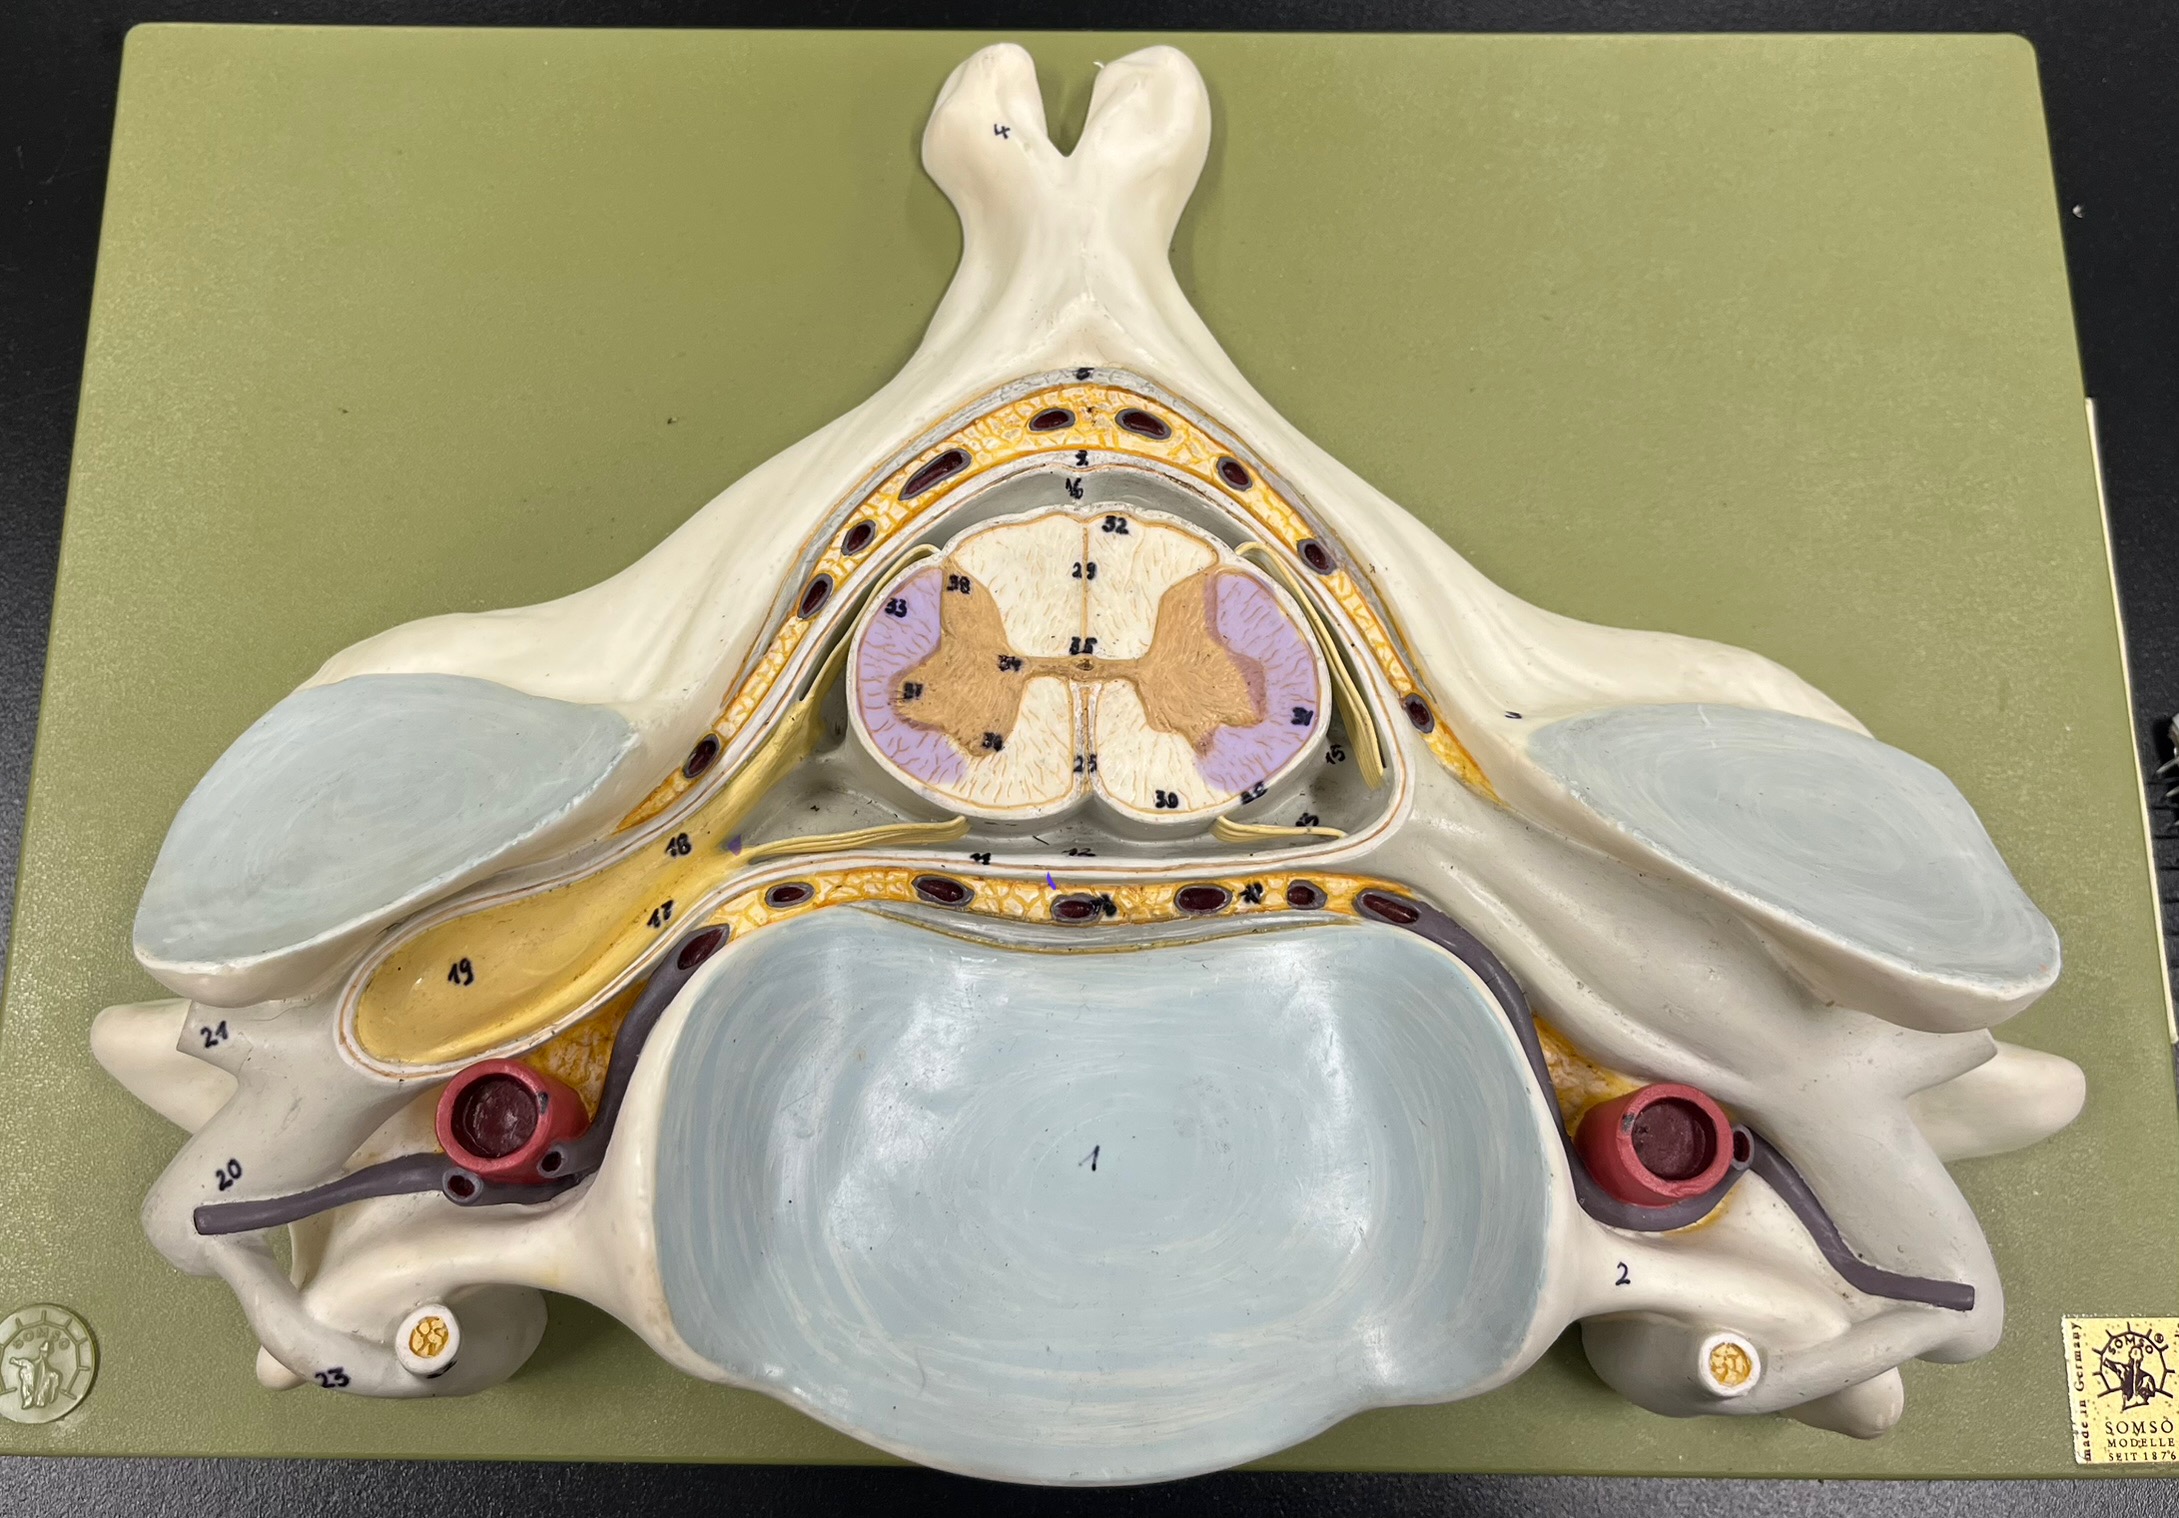

epidural space

dura mater

subdural space

arachnoid mater

subarachnoid space

pia mater

denticulate ligaments

What is the groove here?

anterior median fissure

posterior median sulcus

posterior (dorsal) horn

posterior (dorsal) horn; R—>L

anterior (ventral) horn

lateral horn (selected models)

gray commissure

central canal

anterior column

lateral column

posterior column

white commissure

posterior (dorsal) root ganglion

What is the bulb here?

posterior (dorsal) root ganglion

posterior (dorsal) root

posterior (dorsal) root

anterior (ventral) root

anterior (ventral) root

dorsal ramus

dorsal ramus

ventral ramus

ventral ramus

rami communicantes

rami communicantes

sympathetic chain ganglia

sympathetic chain ganglia